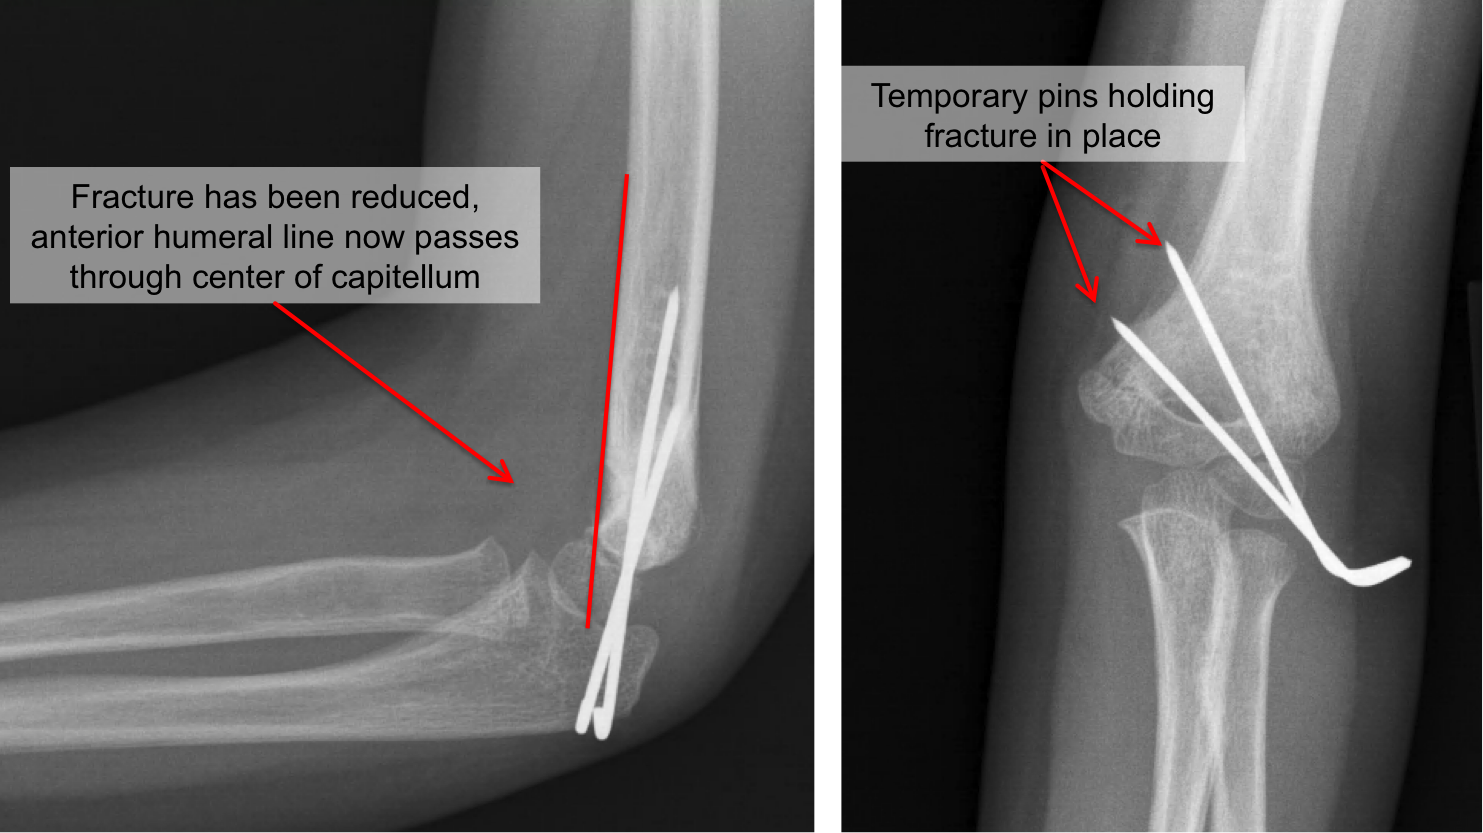

Title : Kid S Elbow Fracture Raleigh Hand Surgery Joseph J Schreiber Md Source : www.schreibermd.com Open New Window